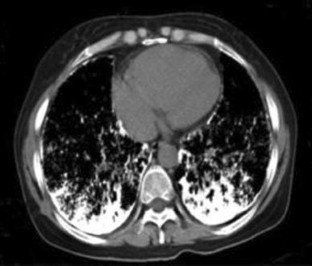

Fig. 1

Fig. 2

Fig. 3

Fig. 4

Fig. 5

Fig. 6

Fig. 7

Fig. 8

Fig. 9

Fig. 10